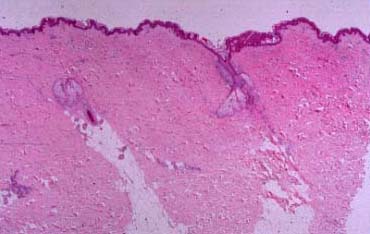

Normal Skin = مقطع في الجلد الطبيعي